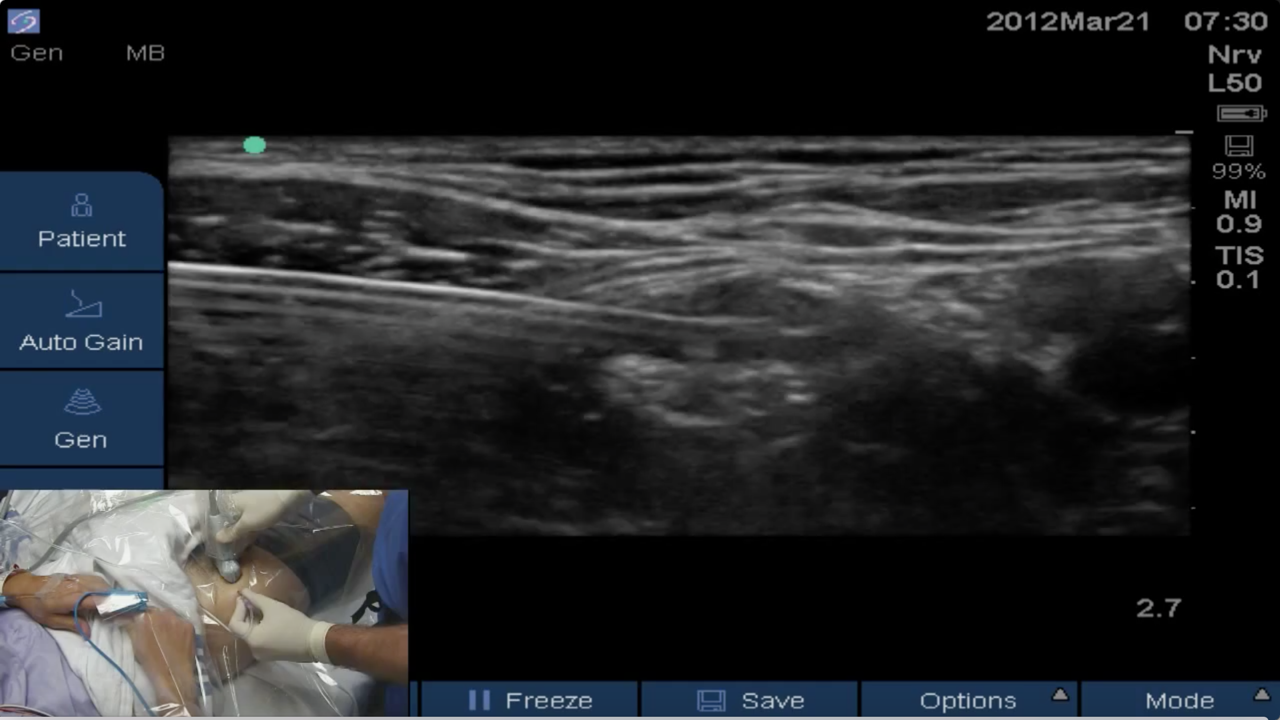

Dr. Stuart Grant, Professor of Anesthesiology at Duke University, describes the anatomy, equipment and technique for the successful placement of an ultrasound-guided femoral nerve block.